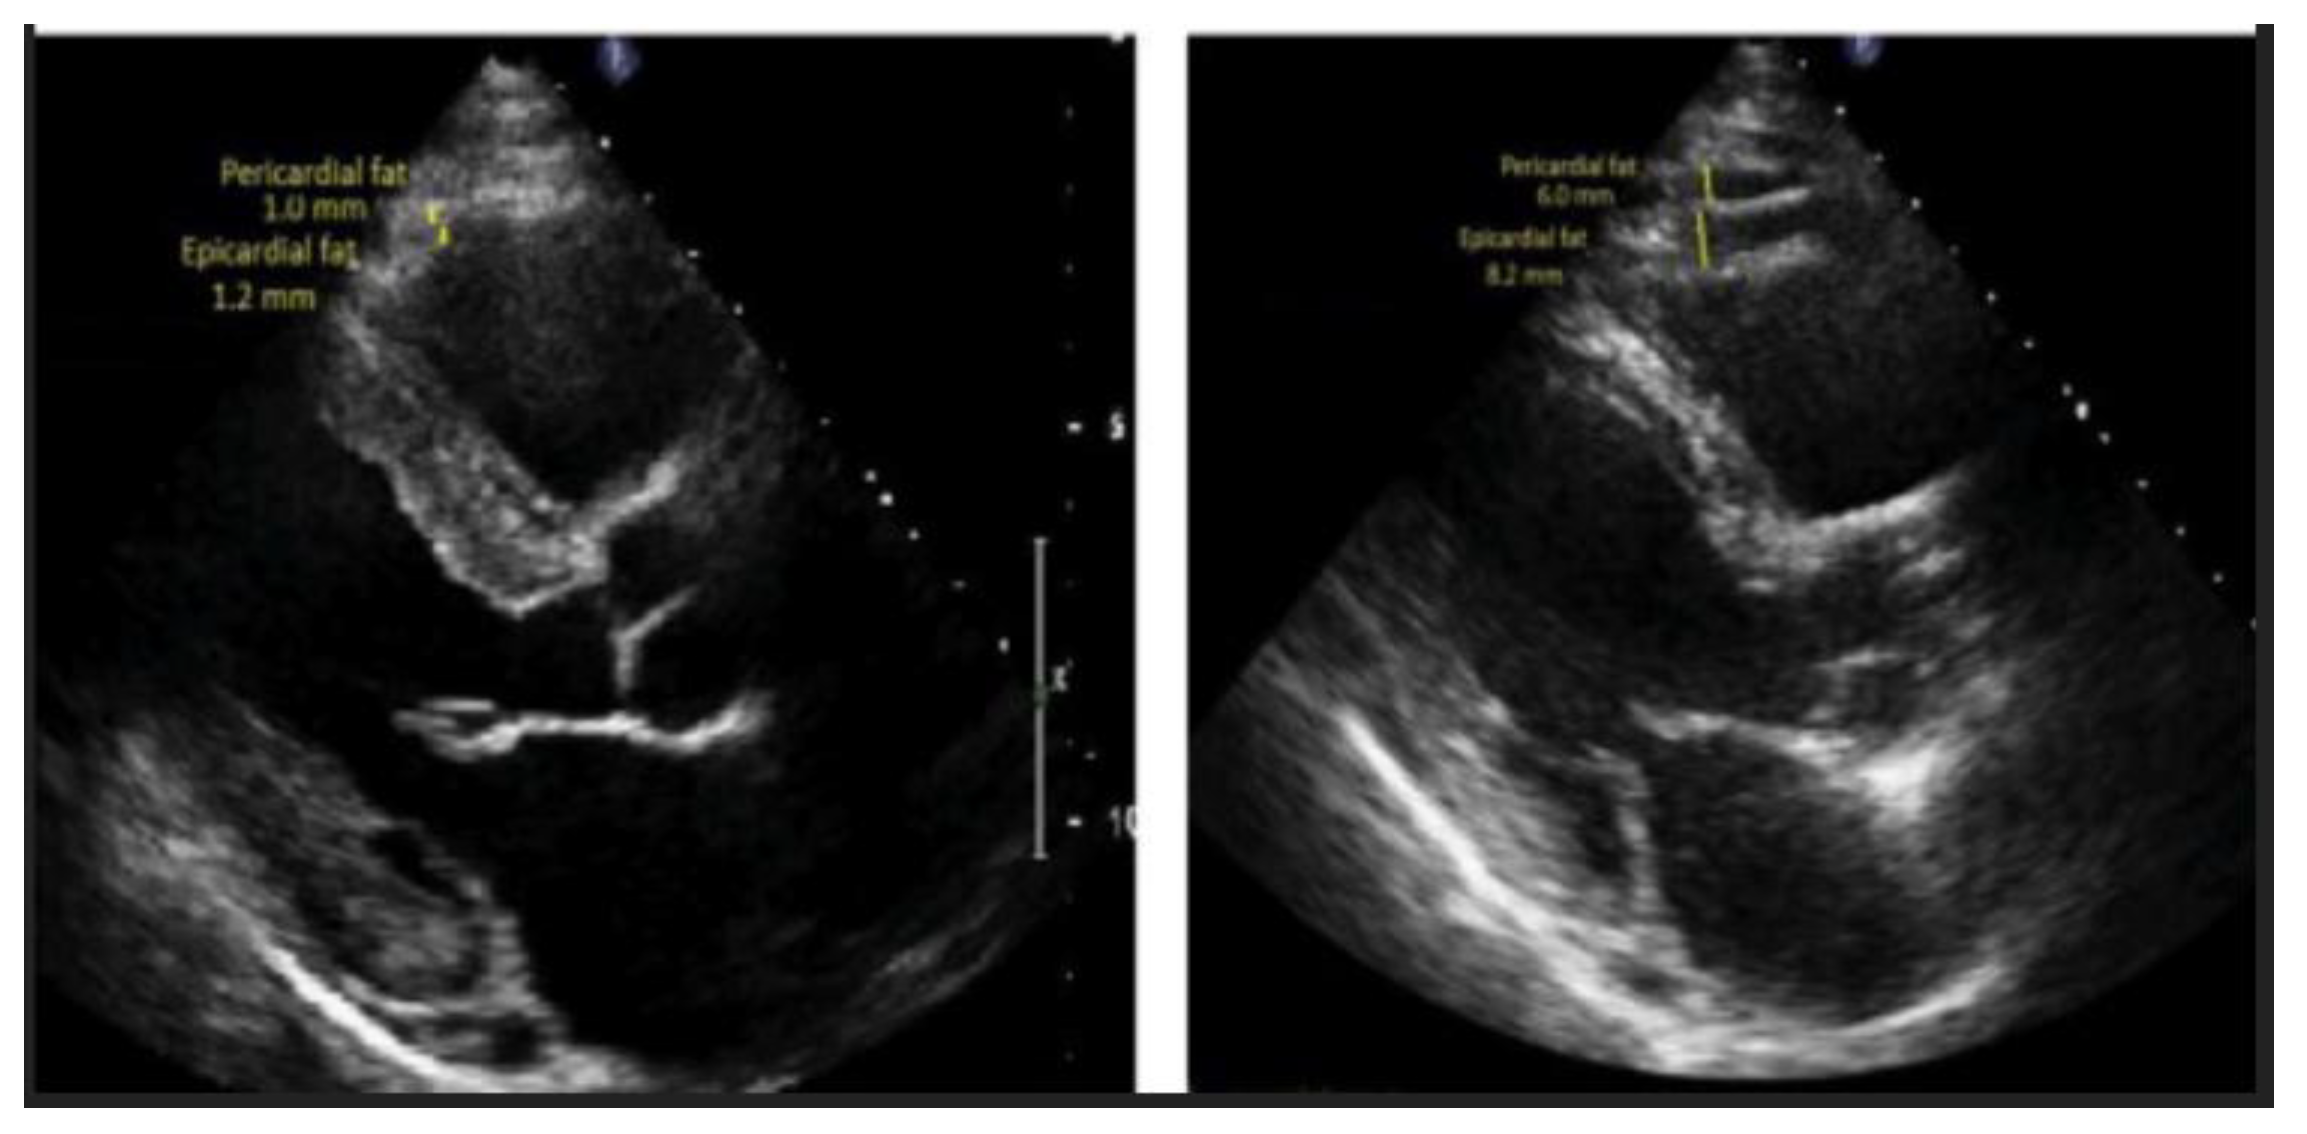

4.4. Echocardiography or Ultrasound (US)

4.4.1. Imaging Techniques

4.4.2. CAT Segmentation

4.4.3. CAT Quantification

4.4.4. Limitations

- Iacobellis, G.; Assael, F.; Ribaudo, M.C.; et al. Epicardial Fat from Echocardiography: A New Method for Visceral Adipose Tissue Prediction. Obesity Research. 2003, 11, 304–310. [Google Scholar] [CrossRef] [PubMed]

- Schejbal, V. [Epicardial fatty tissue of the right ventricle--morphology, morphometry and functional significance]. Pneumologie. 1989, 43, 490–499. [Google Scholar] [PubMed]

- Iacobellis, G.; Willens, H.J.; Barbaro, G.; Sharma, A.M. Threshold values of high-risk echocardiographic epicardial fat thickness. Obesity (Silver Spring). 2008, 16, 887–892. [Google Scholar] [CrossRef] [PubMed]